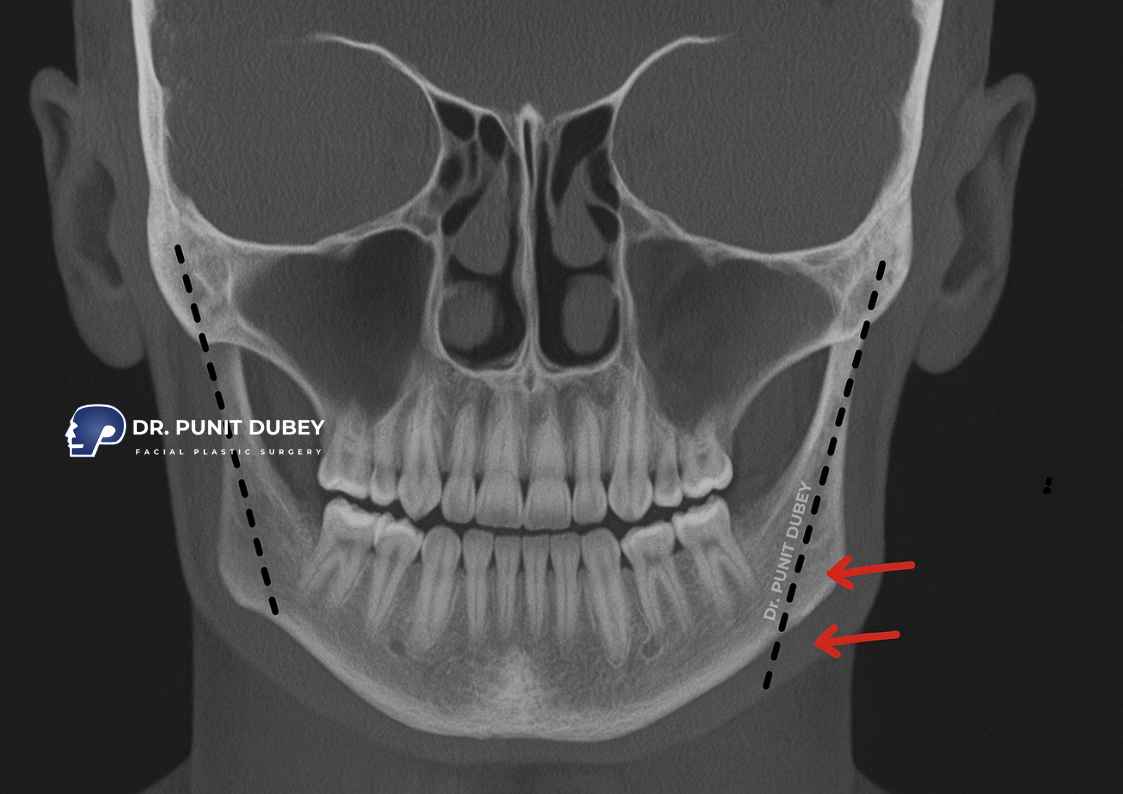

- Examine your jawbone, facial proportions, and bite alignment

- Take 3D scans and facial photos to plan the ideal contour

Technique: Depending on your case, Dr. Dubey may perform:

- The procedure may involve mandibular angle reduction using high-precision instruments such as ultrasonic saws or surgical burrs to contour the bone.

- If needed, Tapering of the mandibular border for a slimmer look

- Sliding Genioplasty if combined with V-Line Surgery

- The jawbone can be reached through a concealed incision inside the mouth or a small, well-placed cut under the jaw — the approach depends on your anatomy and surgical plan.

- Titanium mini plates (if any cuts are made) to stabilize the bone

- Front view improvements: Slimmer jaw width

- 45° angles: Softened transitions from cheeks to chin

- Side profile: Receding mandibular angles and jaw flare

- Under-chin shots: Better definition and no bulk from below